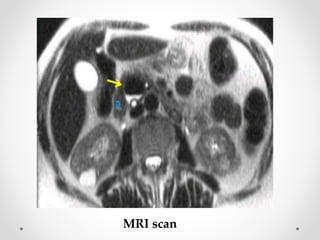

• Magnetic resonance imaging (MRI) studies

MRI scan

Diagnosis • Barium Xrays • Endoscopy • Ultrasonography • Computerized tomographic (CT) scans • Magnetic resonance imaging (MRI) studies